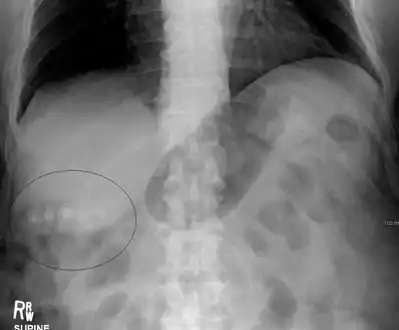

Mixed (brown pigment stones) typically contain 20–80% cholesterol (or 30–70%, according to the Japanese classification system).[35] Other common constituents are calcium carbonate, palmitate phosphate, bilirubin and other bile pigments (calcium bilirubinate, calcium palmitate and calcium stearate). Because of their calcium content, they are often radiographically visible. They typically arise secondary to infection of the biliary tract which results in the release of β-glucuronidase (by injured hepatocytes and bacteria) which hydrolyzes bilirubin glucuronides and increases the amount of unconjugated bilirubin in bile. Between 4% and 20% of stones are mixed.[3]